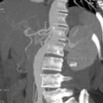

Mass Measurements

在横断位.冠状位.矢状位上分别测量mass的最大径线以及mass的体积测量:

Axial Dmax = 102.9 mm

Coronal Dmax = 100.2 mm

Sagittal Dmax = 80.8 mm

体积:267.467 cm3